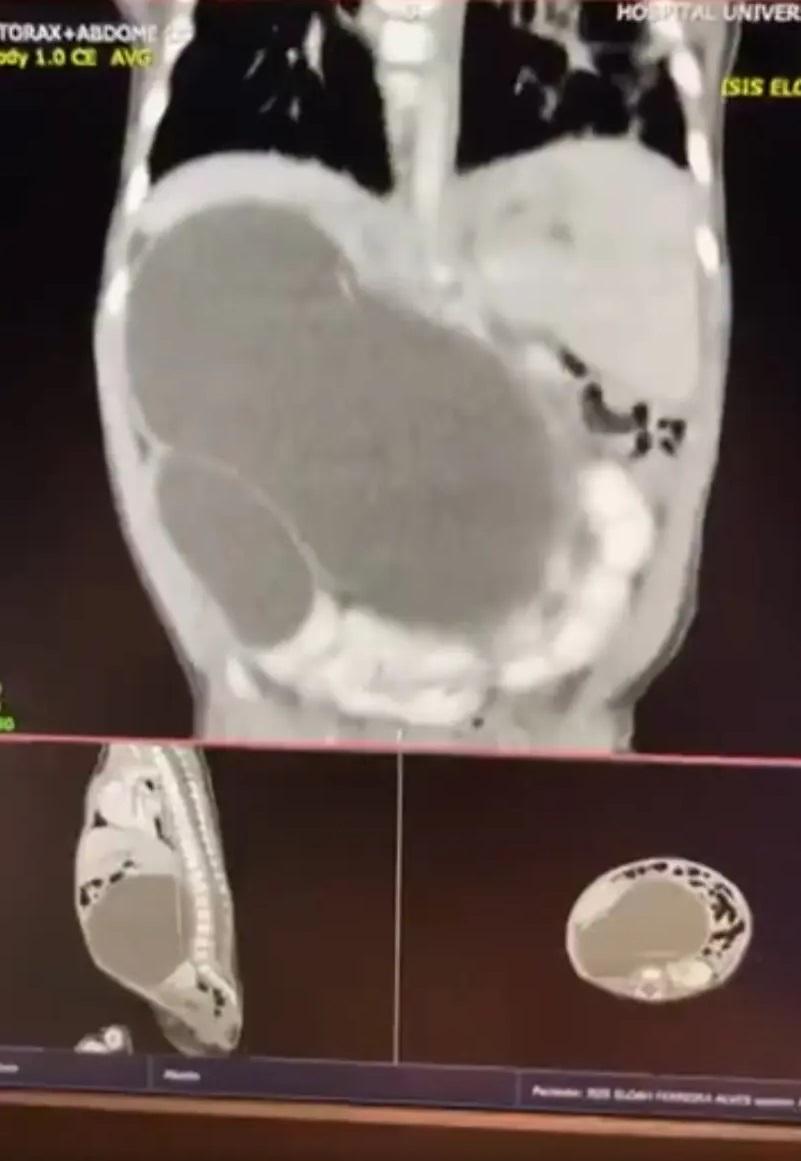

掃描檢查顯示,女嬰天生有4個腎臟。(互聯網)

巴西女嬰阿爾維斯(Isis Alves)天生有4個腎臟,直到5個月大須接受手術時才發現,醫生感到驚訝,稱這是極為罕見的先天性異常,全球醫至今不到100宗。

傳媒報道,母親塔利亞(Thalia)懷孕期間接受產檢,檢查結果已顯示阿爾維斯腎臟異常,但醫生當時無法確定其情況。2022年阿爾維斯在巴西利亞一間醫院早產出生,之後住進育嬰箱,直到5個月大動手術時,才發現原來她長出4個腎臟。

其後,醫生替阿爾維斯切除右上方腎臟,因為其出現阻塞,導致尿液聚積,腎臟增大擠壓胃腸道,令她進食困難。醫生指,剩餘的3個腎臟功能正常。